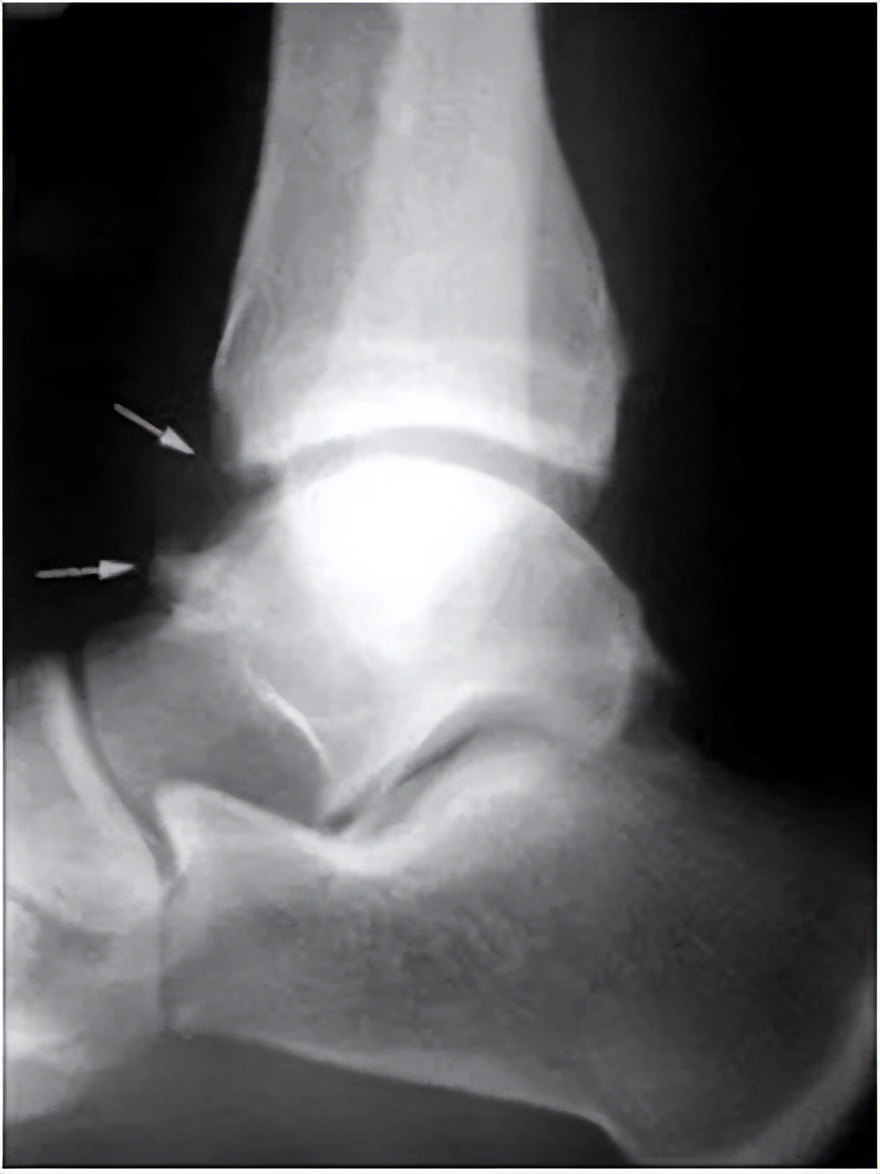

(小康X线片可见胫骨前下缘与距骨颈前上缘骨质增生)

X线检查显示胫骨和距骨颈有骨唇和骨质增生形成,有时可见游离骨体。